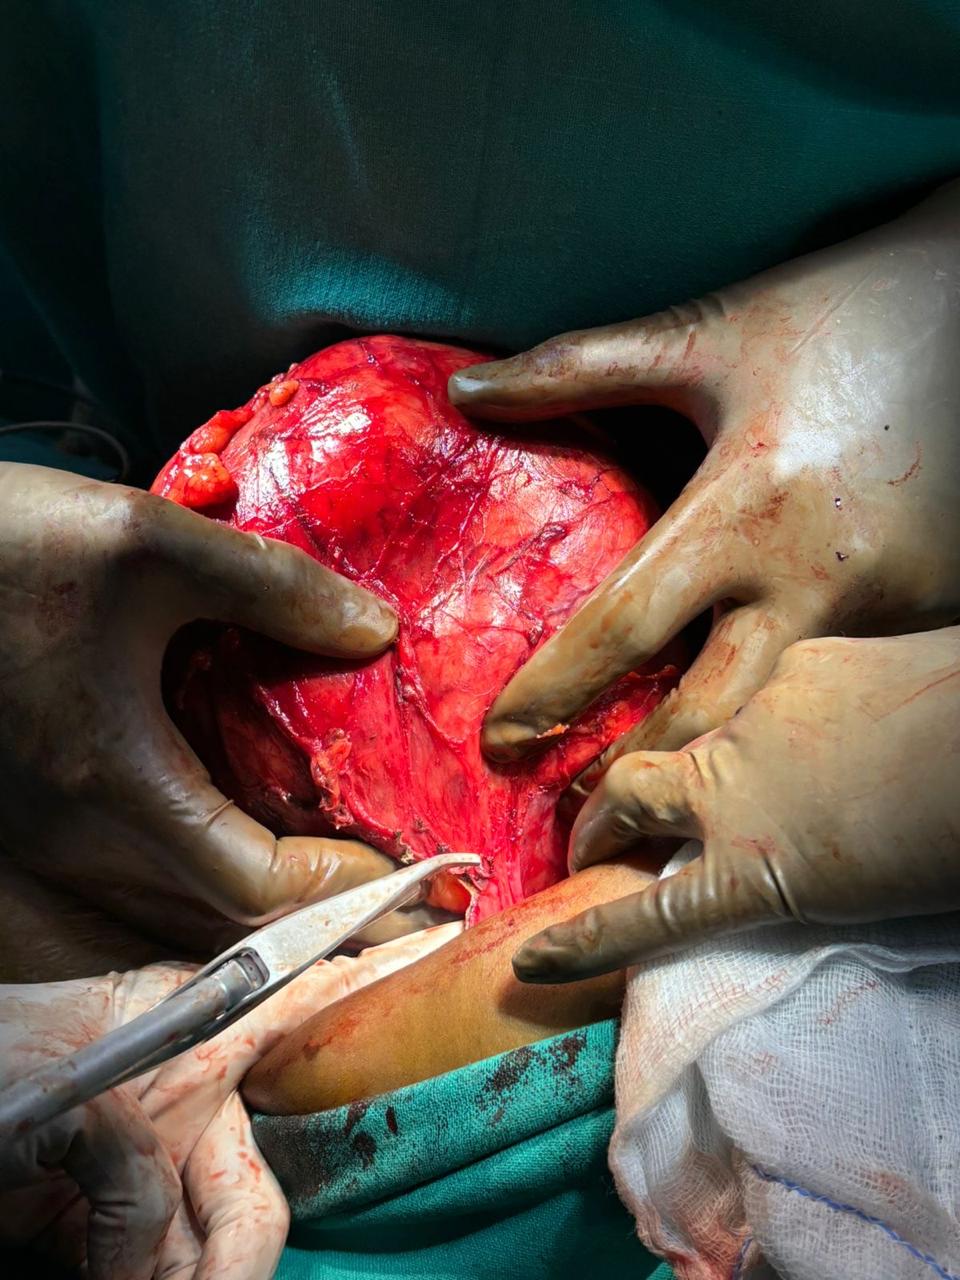

Our Gallery